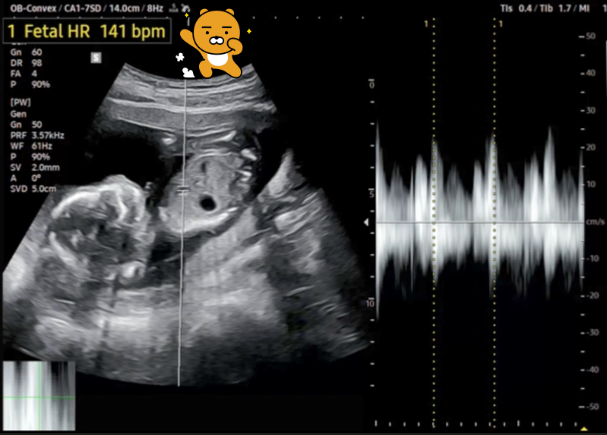

보내준 초음파 영상을 보니... 태아가 움직이기도 해서 정확하게 측정하기가 쉽지는 않아 보입니다.

★ 아기 몸길이(CRL: Crown-Rump Length)는 10.82㎝

★ 아기 머리 직경(BPD: Biparental Diameter)은 3.25㎝

★ 아기 심장 박동수(Fetal Heart Rate)는 141 bpm

★ 임신 주수(GA: Gestational Age)는 올해 6월 말로 되어 있습니다. 그런데 CRL과 BPD 측정값에 따라 임신 주수와 출산 예정일이 좀 다른 것 같네요. 뭐 며칠 사이이기는 합니다.

[왼쪽-몸길이와 머리 직경, 오른쪽-심장 박동수]

총 4분 정도 되는 초음파 영상인데 이중에는 허벅지 뼈 길이(FL: Femur Length)와 머리 직경(BPD)의 비율도 있던데, 이 비율로 아기의 체중을 산출한다고 하는데 그건 몰라서 통과했습니다.